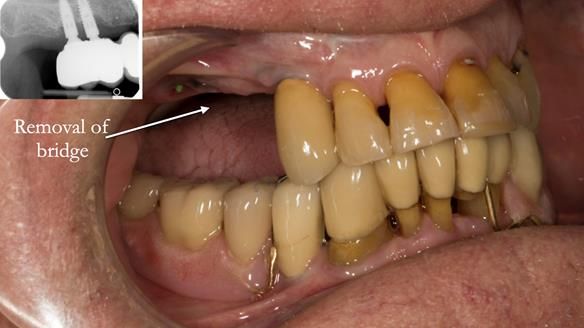

In the upper arch:

- a failing upper left tooth supporting a bridge was removed

- an implant-supported bridge on the upper right was dismantled

A metal-based upper RPD was made,

with metal backings incorporated to future-proof the design

should further teeth fail.

This case was always about function, not aesthetics.

Ken’s teeth were never going to look perfect.

There were stained composites, old restorations, and obvious wear.

That was accepted from the outset.

The way Rowan lengthened the teeth — particularly in the upper RPD — to match the existing gingival recession on the remaining teeth was superb. The dentures sit naturally within the context of the rest of the mouth.